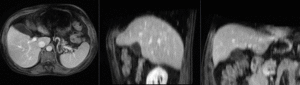

affine registered MRI & CT

nonrigid registered MRI & CT